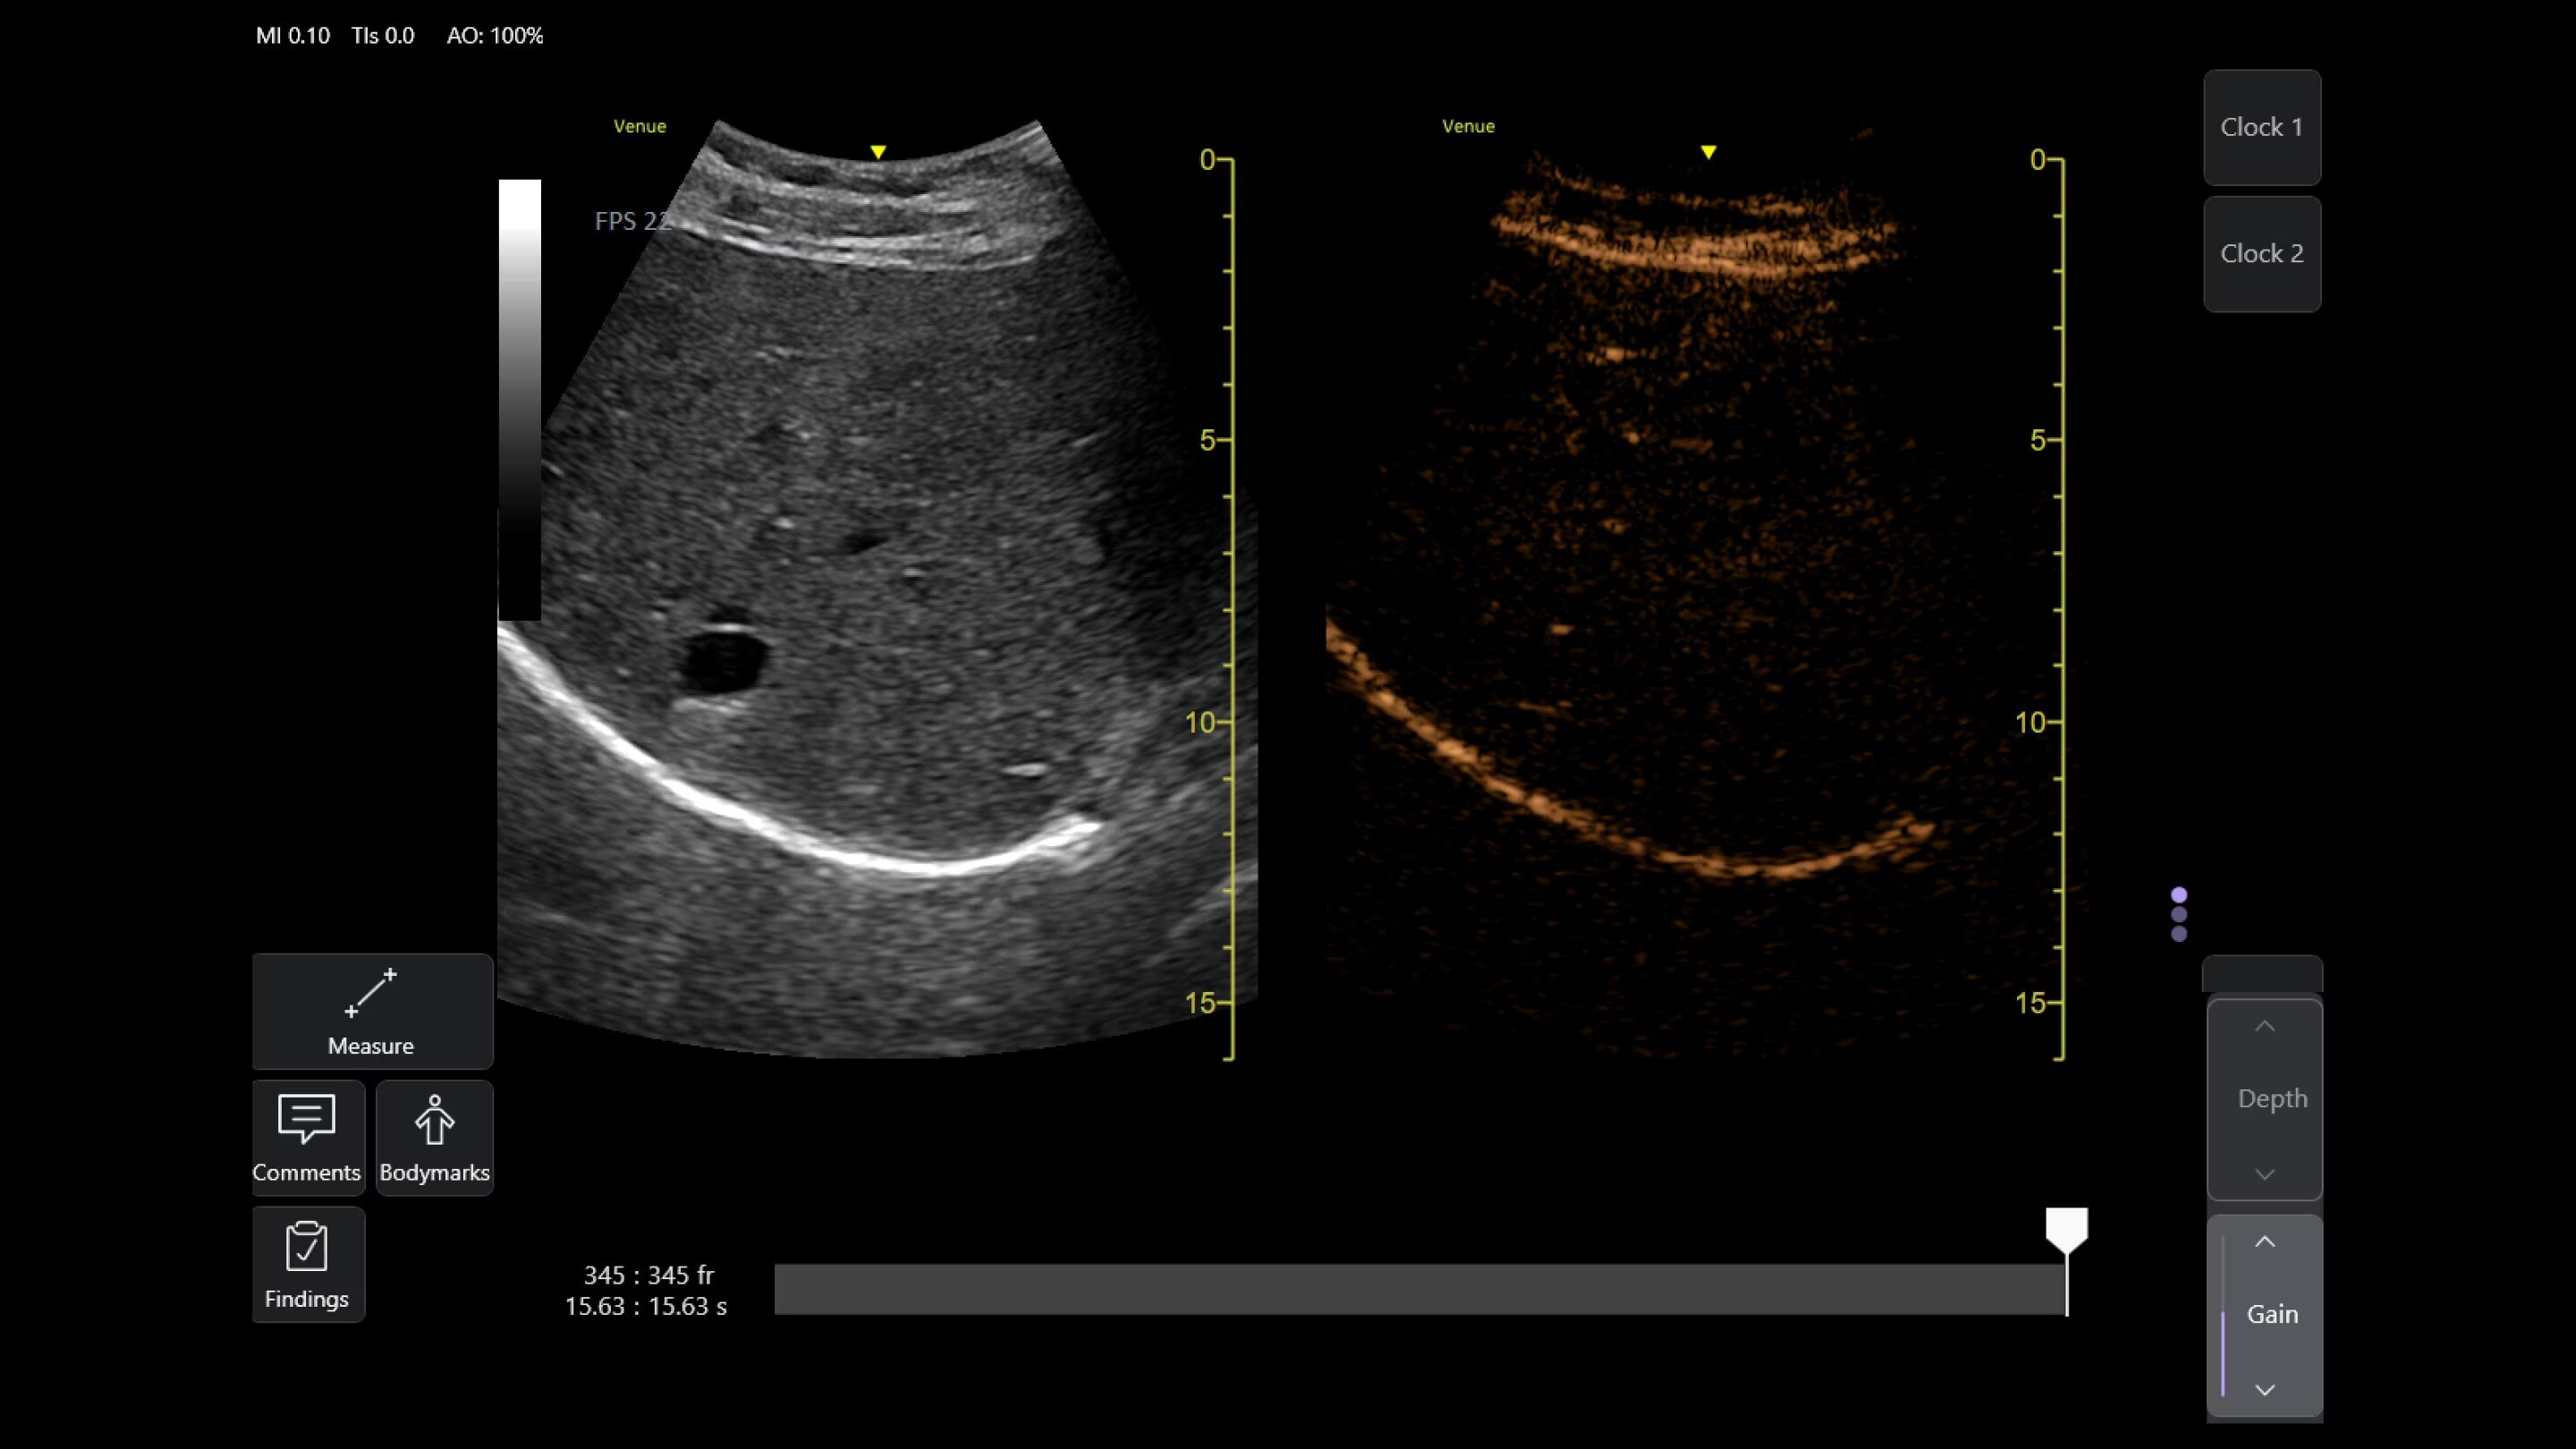

AI-enabled Auto Bladder Volume

Auto Bladder Volume provides rapid and easy urinary bladder volume measurements, saving clinicians valuable time and enhancing clinical accuracy. It measures bladder dimensions and calculates the bladder volume from two views: transverse and longitudinal.